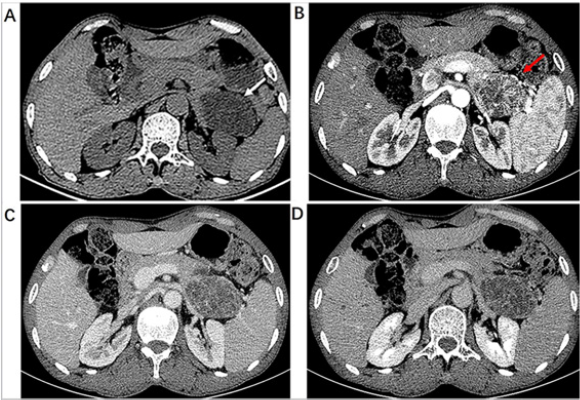

Informed consent for publication was obtained from the patient. A 62-year-old male was referred to our hospital after experiencing upper abdominal discomfort for one month. There was no special medical history. Physical examination was normal. Laboratory tests included complete blood counts, serum amylase and lipase, coagulation function, fasting blood glucose, AFP, serum CA19-9 in the normal range; CEA was increased slightly to 3.53ng/ml. An abdominal CT scan showed a well-circumscribed multilocular cysts lesion with septa measuring 6.3cm×4.2cm×4.4cm in the tail of the pancreas (Figure 1A). Markedly enhanced septa in the shape of spoke-wheel were observed after injection of contrast agent (Figure 1B). The degree of lesion enhancement was decreased at portal vein phase (Figure 1C) and delayed phase (Figure 1D).

Figure 1: 62-year-old male with pancreatic hemangioma. (A) Plain CT scan of upper abdomen showed well-circumscribed multilocular cysts with septa lesion in the tail of the pancreas (white arrow). (B) Enhanced CT scan at arterial phase demonstrated a mass with markedly enhanced septa in the shape of spoke-wheel (red arrow). Portal vein phase (C) and delay phase(D) showed the enhanced reduction of the separations.